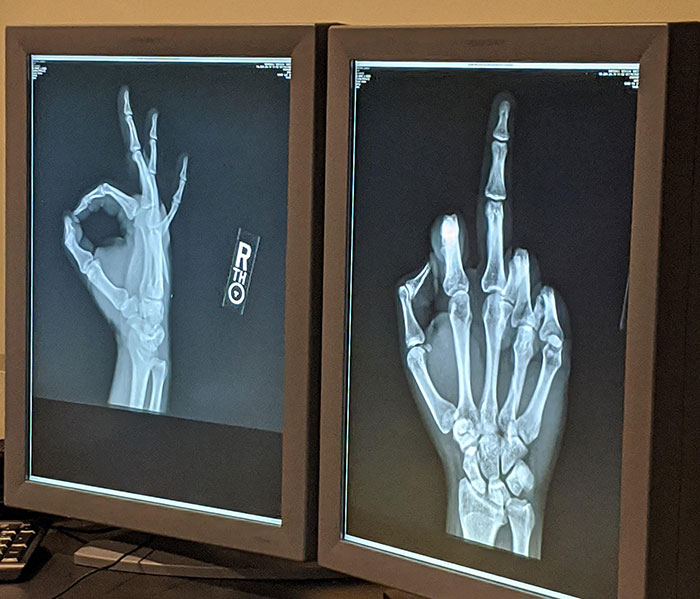

I Give This Post Two Thumbs Up